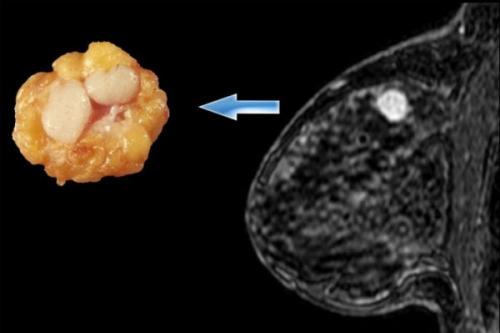

называют фиброаденоматоз (представлен на фото).

Эта патология характеризуется быстрым разрастанием железистой ткани с образованием кист, заполненных жидкостью.

Фиброзно-кистозная или диффузная мастопатия – поражение молочной железы в виде новообразования. Опухоль имеет гормональную природу и возникает чаще всего в результате нарушения баланса эстрогена и прогестерона в организме женщины.